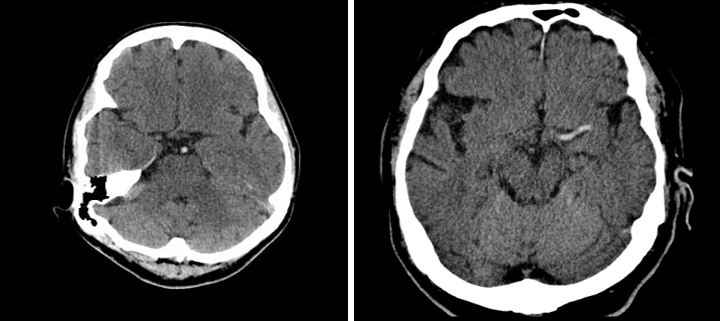

Cerebral infarct in the left cerebral hemisphere

Hyperdense middle cerebral artery sign in stroke

CT head (without contrast; axial plane)

The left middle cerebral artery is hyperdense as a result of thromboembolic occlusion. Hypodensity with loss of gray-white matter differentiation in the left frontal, temporal, and parietal regions corresponds to an acute infarct in the middle cerebral artery distribution.